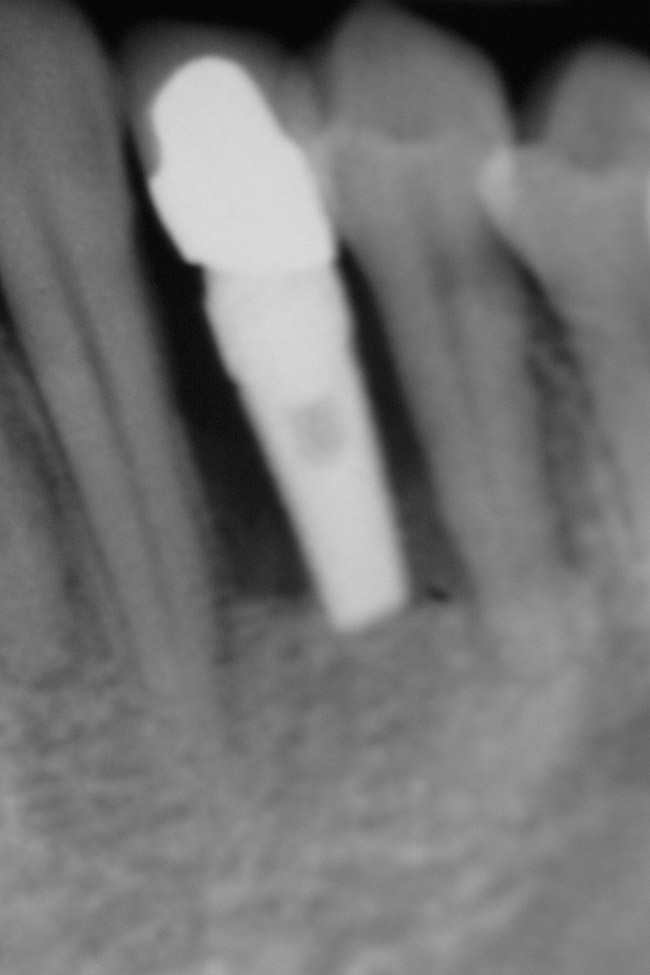

Figure 10  Radiograph of orthodontic distraction osteogenesis.

Figure 10

Figure 11  Radiograph showing developed implant site of tooth No. 23.

Figure 11

Figure 16  A cross-sectional view of postorthodontic site development at No. 23 position. Sufficient bone has been developed to accommodate implant placement in an optimal prosthetic position. Simultaneous GBR is planned at the coronal most portion of the implant per anticipated dehiscence.

Figure 16

Following the first goal of orthodontia—moving tooth No. 22 to a proper functional and anatomical position—a periodontal reevaluation was performed, demonstrating an improvement in short- and long-term tooth prognosis. At this time, the decision was made to abort continual extrusion of teeth Nos. 21 and 22, although some attachment level discrepancy remained between Nos. 21 and 22 (Figure 14). Implant diagnostics ensued and included mounted study models and a diagnostic wax-up. A scanning appliance was created to demonstrate the desired prosthetic outcome requirements, and the patient was referred for computed tomography (CT) scans. CT scan assessment demonstrated successful orthodontically directed GBR to allow implant placement (Figure 15 through Figure 16). Only minor GBR therapy would be needed and could be accomplished simultaneously with implant installation. Guided implant placement occurred, using an open flap approach (Figure 17). During surgery, root dehiscences were noted on teeth Nos. 21, 22, 24, and 25, as well as the anticipated dehiscence following implant placement at No. 23 (Figure 18). A positioning reference (index) was secured after implant placement to facilitate a provisional prosthesis at stage II surgery. Cortical perforations then were placed adjacent to the implant to encourage angiogenesis (Figure 18), and mineralized freeze-dried bone allograft enhanced with platelet-derived growth factor was placed over the dehiscences for purposes of guided tissue regeneration and GPR (Figure 19). A highly resorbable collagen membrane was placed to stabilize the allograft. The flap was coronally repositioned, and primary-intention wound healing was achieved (Figure 20 and Figure 21). Following 4 months of stage I surgery, implant uncovery and immediate provisionalization was performed in conjunction with connective tissue grafting. Final orthodontic tooth movement then ensued, using the implant as anchorage to optimize end-tooth movements, interroot separation, and the cuspid-protected occlusal scheme. A final impression then was secured, and a zirconia abutment (Figure 22) with an all-ceramic restoration was fabricated for the prosthetic phase completion of No. 23 (Figure 23] through Figure 25).